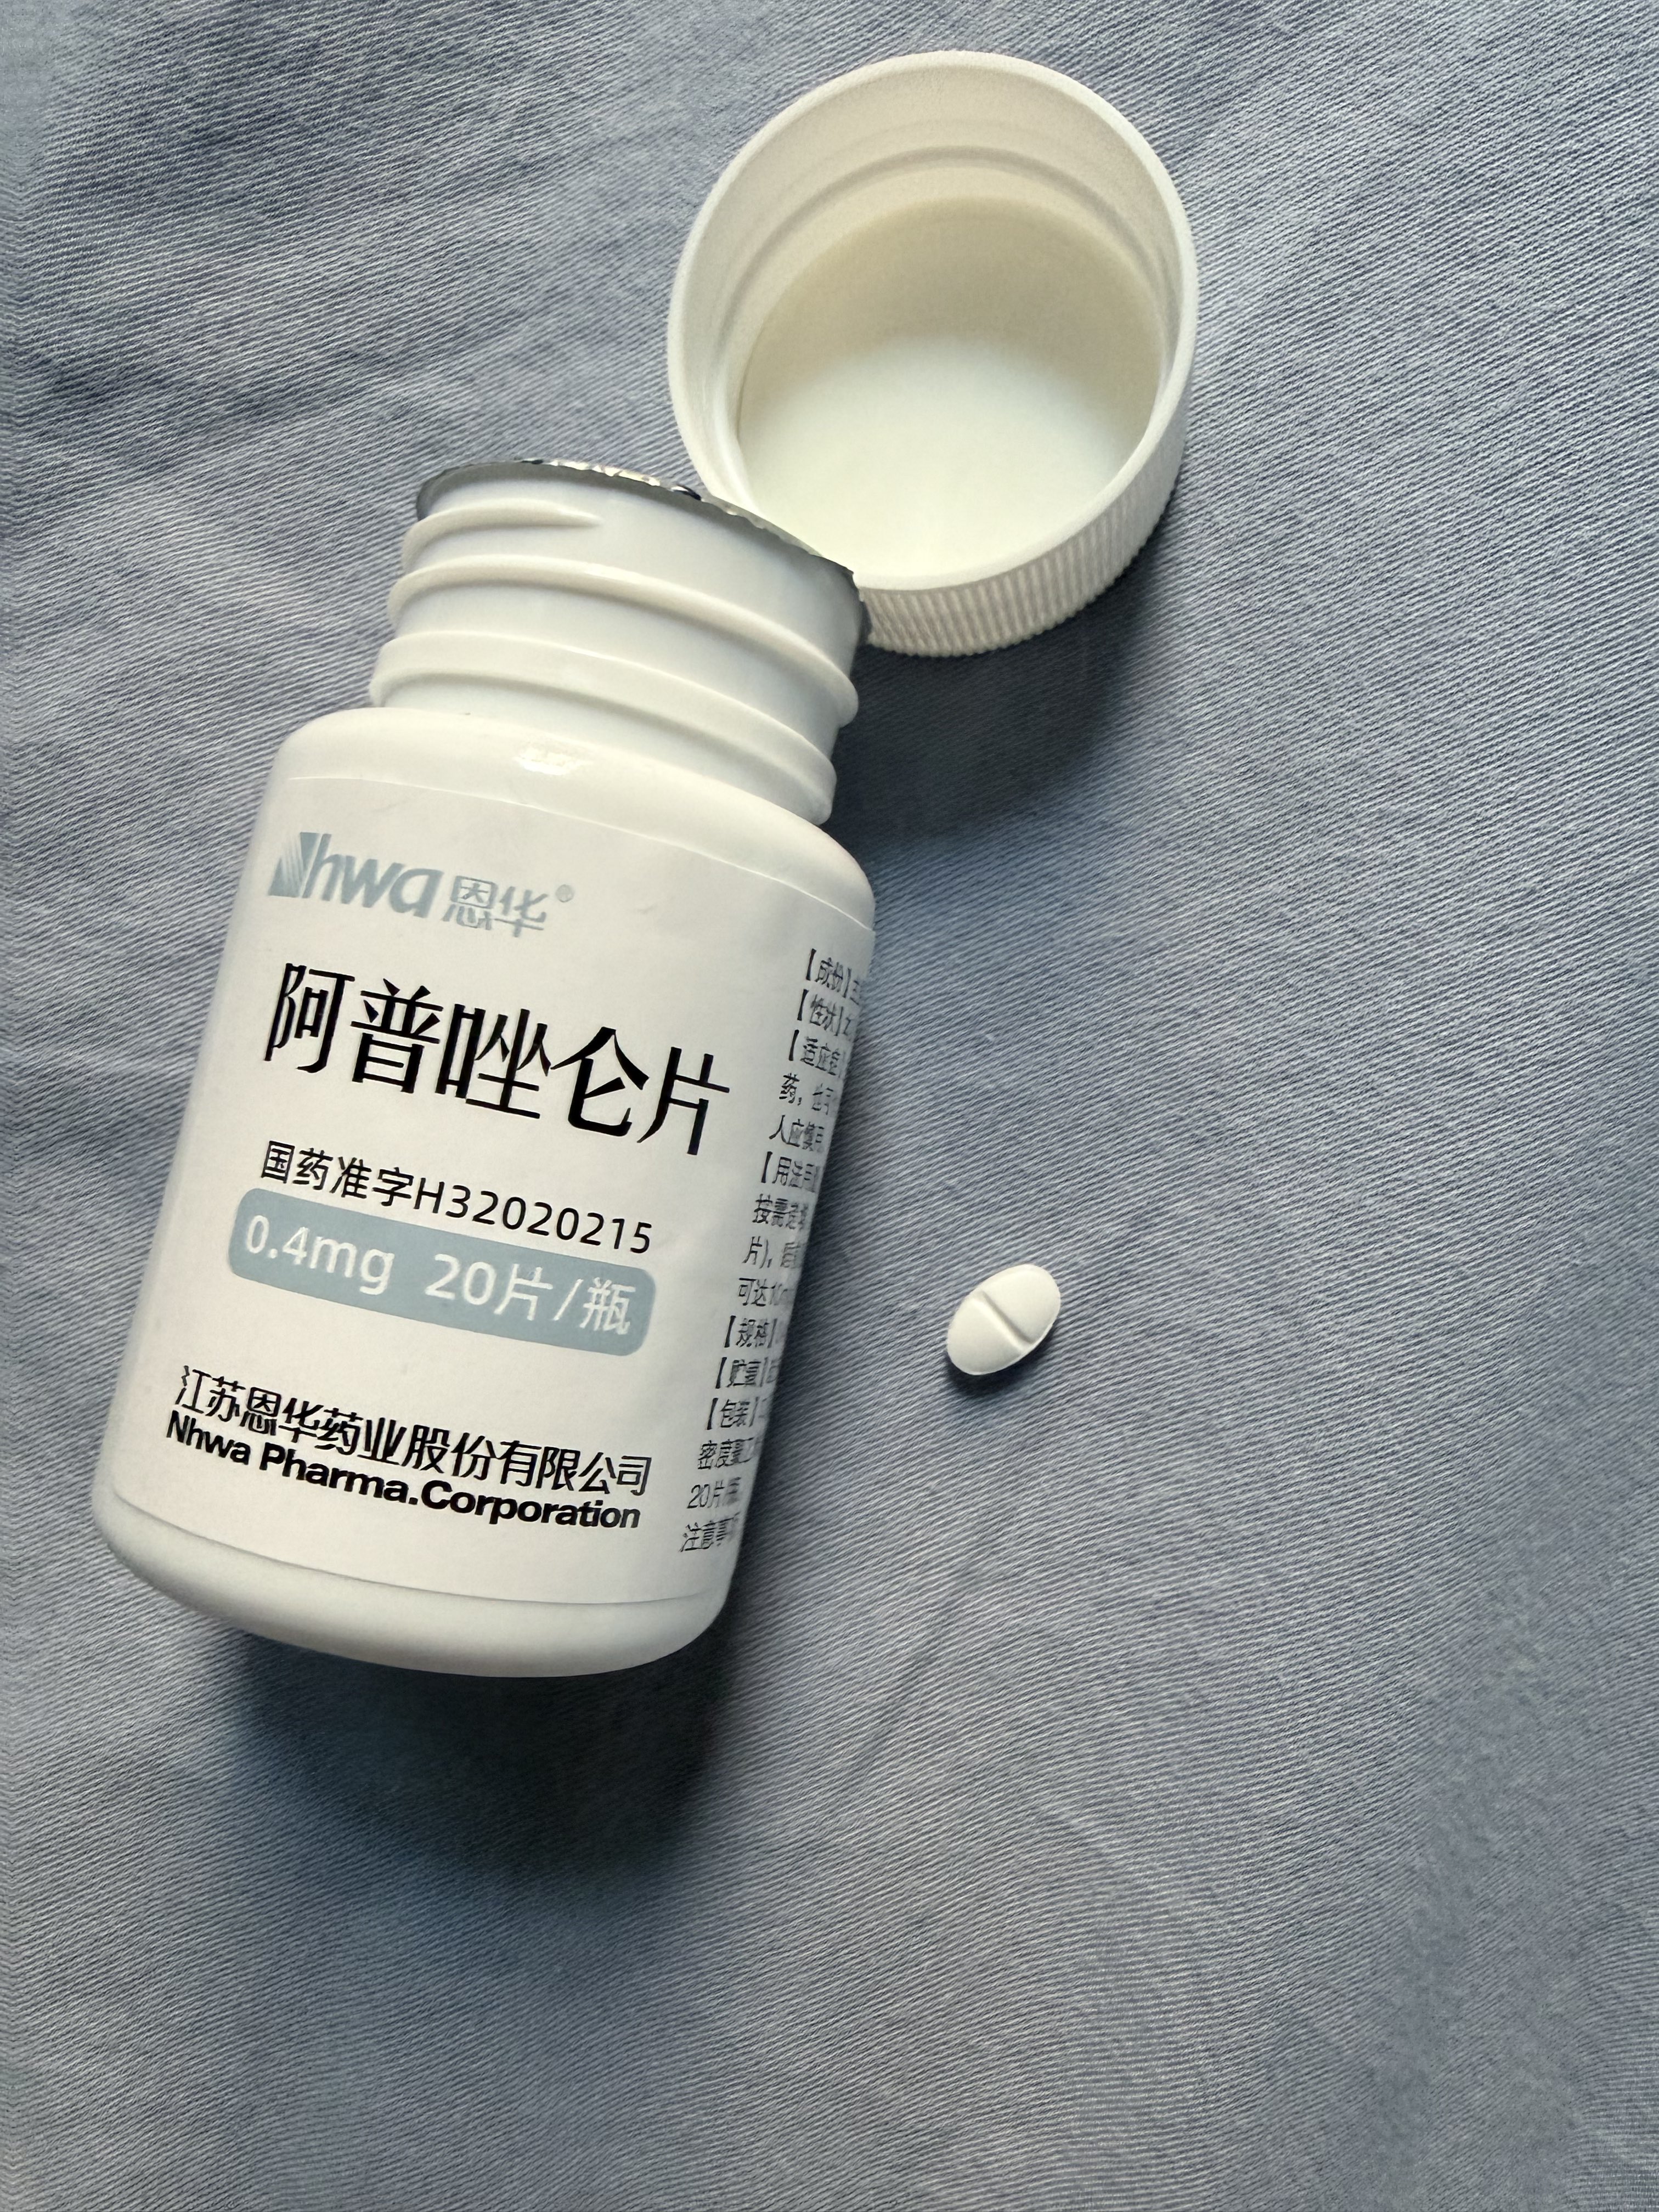

炽烈已极 @AnIncandescence已知阿普唑仑对伴有恶心呕吐症状的过量有额外作用,它本身有联用其他药物治疗化疗引起的恶心的用途。